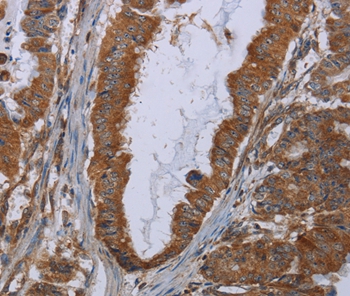

图片:

Immunohistochemical analysis of paraffin-embedded Human esophagus cancer tissue using #36556 at dilution 1/30.